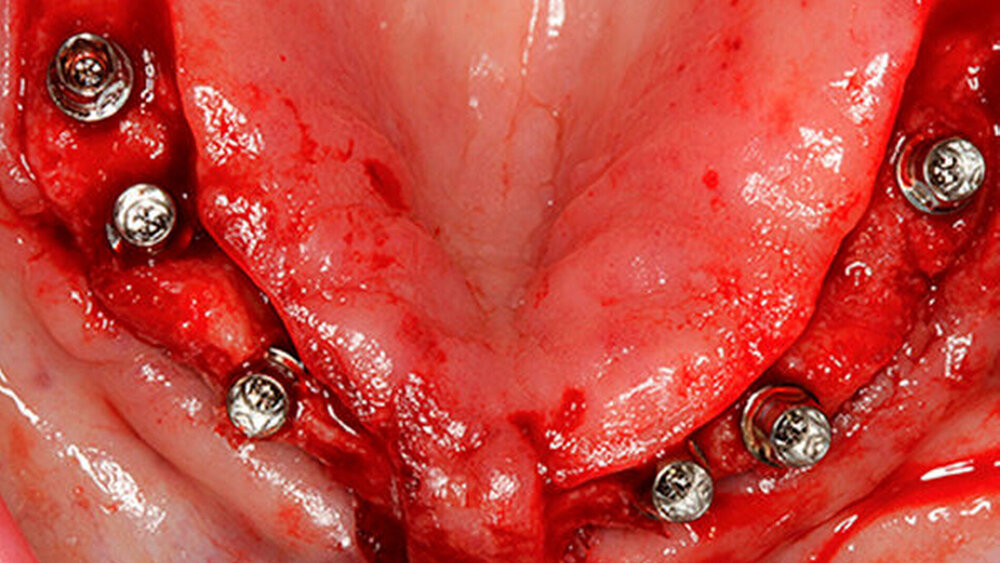

Eine 67 Jahre alte Patientin stellte sich mit dem Wunsch einer Oberkiefersanierung in unserer Praxis vor. Ihre Restzähne waren aufgrund von Parodontitis und funktioneller Überlastung nicht mehr erhaltungswürdig. Wir ließen sie bis kurz vor der definitiven Versorgung als strategische Pfeilerzähne für die Interimsprothese in situ.

Die dreidimensionale Positionierung und die richtige Anordnung der Implantate sowie des Zahnersatzes. Es ist wichtig, eine prächirurgische prothetische An- und Sprechprobe (Set-up) durchzuführen, um die Implantatpositionen und -achsen korrekt nach der späteren Prothetik zu bestimmen und auszurichten.

Das hat nichts mit den unterschiedlichen Protokollen zu tun. Der Übergang zwischen Restauration und dem Abutment darf nicht sichtbar sein, egal bei welchem Protokoll. Entweder werden die Implantate deshalb tiefer gesetzt oder der Knochen wird abgetragen. Unproblematischer ist das im Unterkiefer, die Lippe und die Lippenbänder verdecken viel. Wir implantieren – wann immer das geht – erst in der 3er-, 4er-, 5er-Position, nicht direkt in der Front.